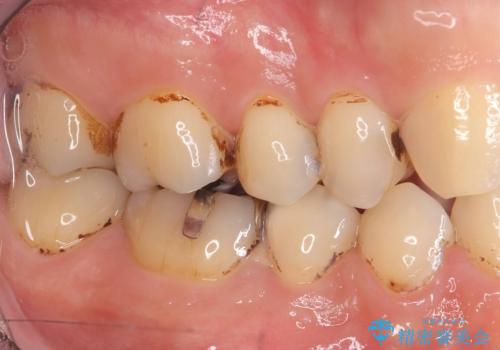

- 虫歯が大きく歯が欠けている状態でした。 そこに食べ物も詰まっている状態でした。

虫歯を除去後、精密根管治療を行い、オールセラミッククラウンで治療を行いました。

虫歯が大きく神経まで到達していました。将来根尖性歯周炎にならないよう徹底的に神経をとり洗浄したうえで被せ物をしています。